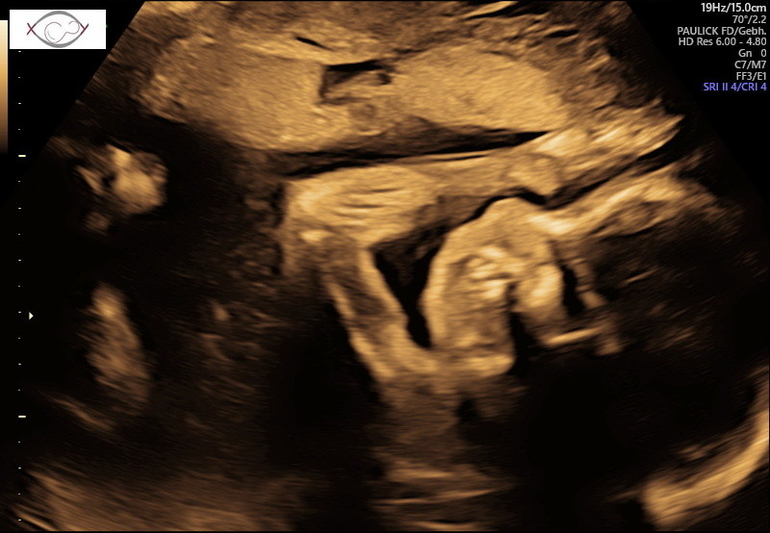

Теперь я особо ничего уже не боюсь👍 2,5 недели назад писала пост о не полном предлежании плаценты, она за это время поднялась и уже 2,5 см от зева🤗Ура, ура, ура🥳🥳🥳 Особо беременной себя до сих пор не чувствую, в том плане, что ни отёков, ни какого то дискомфорта пока не ощущаю, но жду, готовлюсь морально🤪. Для папы нашего сделали фото писюна, чтобы уж точно он уже был уверен, что мальчик😅🤣🤣🤣 Пяточку, которой малой мне пиночки отвешивает и личико попытались сфоткать, но скромняшка всё ручками закрывался.